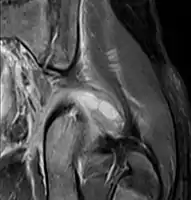

Coronal fat suppressed post contrast image showing a multiloculated bacterial abscess in the left gluteus minimus muscle due to tropical pyomyositis. Coronal fat suppressed post contrast image showing a multiloculated bacterial abscess in the left gluteus minimus muscle due to tropical pyomyositis.